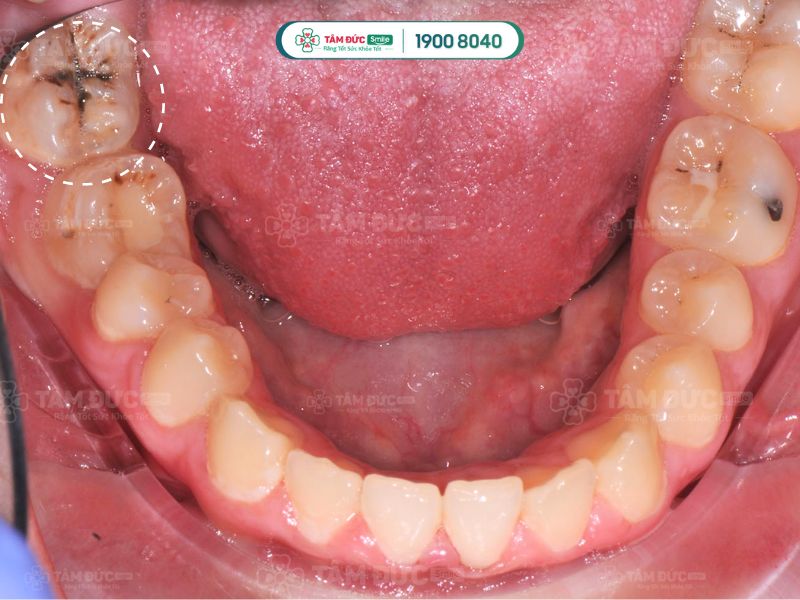

Sâu răng là nguyên nhân chủ yếu làm cho kẽ răng bị đen. Đây là bệnh lý răng miệng phổ biến, là hiện tượng mô cứng trên răng bị tổn thương trước sự tấn công của vi khuẩn. Các lỗ nhỏ li ti hình thành trên bề mặt răng, dần phát triển thành lỗ sâu răng to có màu đen, có thể nhìn thấy bằng mắt thường.

Sâu răng thường hình thành ở kẽ răng. Do đó, nếu Quý khách nhận thấy kẽ răng của mình bị đen thì có thể nghĩ ngay đến là do sâu răng gây ra.

Kẽ răng bị đen do sâu răng gây ra